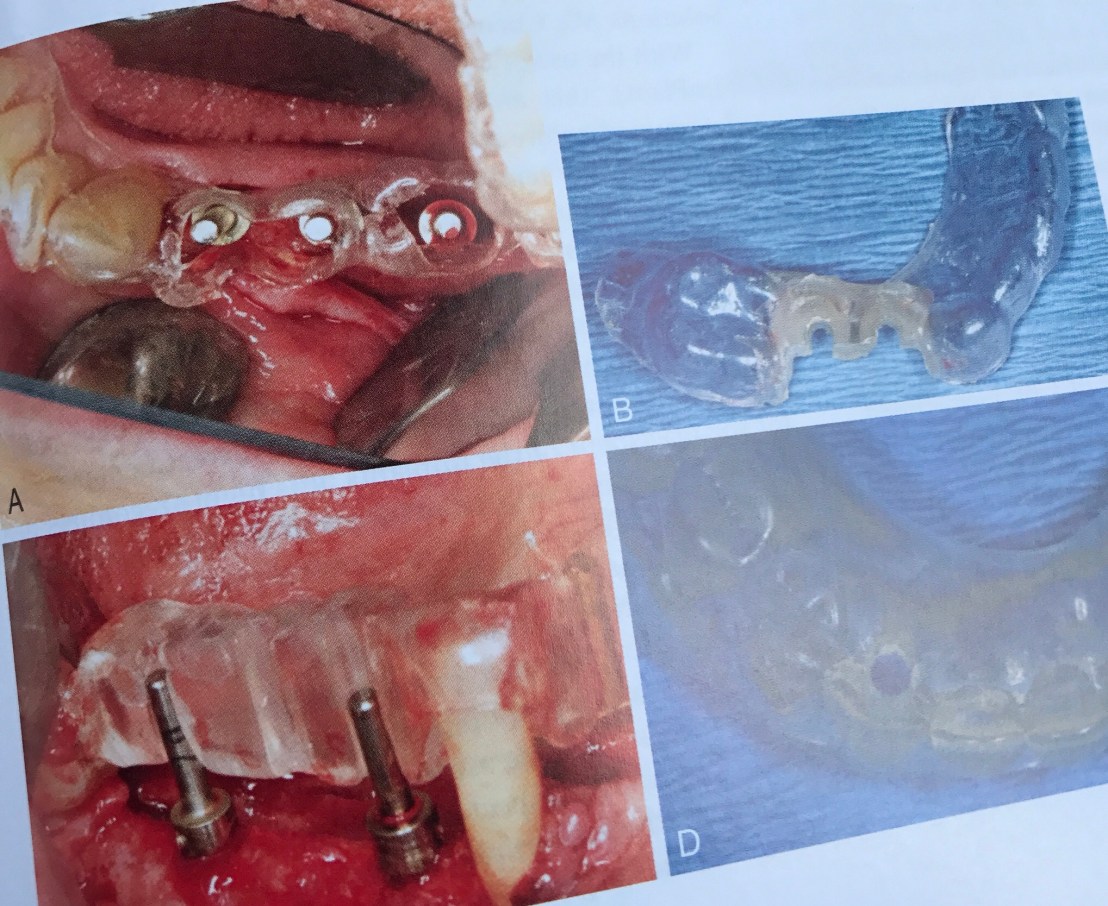

แสดงการสร้าง Surgical stent ที่มี accurate น้อยเกินไป (Nonliming design)ทำให้การวางตำแหน่งพลาดได้ง่าย

ไม่สามารถวาง Angulation ได้เลย

อันนี้คือ Stent ที่ accurate ขึ้น (Partial limiting design) แต่ยังจำกัดตำแหน่งในการวางหัว drill ในขั้นตอนท้ายๆ ทำให้มีโอกาสผิดพลาดในแนว Bucco-lingual ได้สูง

Stent ชนิดที่ accurate มากขึ้นไปอีกคือ Complete limiting design ครับ และเหนือไปกว่านั้นคือ CBCT Surgical Guides

CBCT Surgical Templates จะแบบออกเป็น 3 ชนิด ตาม accuracy คือ 1.Tooth-supported > 2.Bone-supported > 3.Tissue-supported

อันนี้คือ Surgical stent ที่ locate ตำแหน่ง Mand canal และ Mental foramen ลงไปด้วย เป็น stent ที่ลอกรายละเอียดทั้ง Bone, tooth อยู่ในตัวเดียวกัน